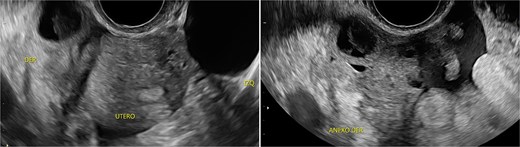

Stage III pelvic inflammatory disease (PID) was suspected based on ultrasound (Figs 1–3) and gynecological examination, which revealed mild bulging of the right lateral fornix, cervical motion tenderness, and a white, non-foul-smelling vaginal discharge. Empiric intravenous antibiotic therapy was initiated, followed by exploratory laparotomy via a Pfannenstiel incision. Intraoperative findings included an 8 × 5 cm uterus, edematous fallopian tubes, and a simple 5 × 5 cm left adnexal cyst. Cystectomy was performed.

Transpelvic ultrasound reveals a heterogeneous mass adjacent to the right adnexa measuring 4.6 × 8.4 cm, predominantly hypoechoic with anechoic areas.

The cervical motion tenderness—a minimum diagnostic criterion—along with fever and elevated CRP, led to a misdiagnosis of PID, with the ultrasound mass interpreted as a tubo-ovarian complex. Retrospectively, both low-normal hemoglobin and absence of mucopurulent cervical discharge were notable. When mucopurulent discharge and leukocytes on vaginal wet prep are absent, PID is unlikely, and alternative diagnoses should be considered [6].

IMTs lack distinctive imaging characteristics. Ultrasound often shows increased vascularity. Contrast-enhanced computed tomography is the imaging modality of choice for gastrointestinal IMTs, which typically present as hypodense, heterogeneous, well-defined masses frequently mistaken for colorectal carcinoma [7].